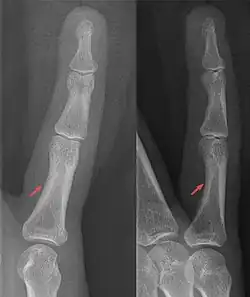

Von Anfängern kann das Foramen nutricium auf einer Röntgenaufnahme als Schrägfraktur des Knochenschafts fehlgedeutet werden, da es sich röntgenologisch selten deutlich darstellt.